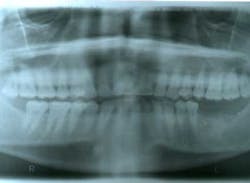

Ten months after the GBR procedure was done, a new panoramic radiograph (Fig. 4) was taken and the site was reentered for implant placement into an ideal restorative position. Dental implants (nobel active 5.0 x 11.5 mm) were placed at the No. 18 and No. 19 positions (Fig. 5), into excellent type I dense bone; note that the majority of the dental implants are completely housed in newly grafted bone. Additional minor bone grafting was done using autogenous coagulum collected during the osteotomies and a xenograft particulate (Bio-Oss, Geistlich), then covered with a resorbable collagen membrane (Biogide, Geistlich) in order to maintain buccal bone stability and contour (Fig. 6). The implants were later uncovered, ensuring that an adequate zone of keratinized tissue was present and the implants were subsequently restored (Figs. 7, 8). The success of this case was dependent upon proper treatment planning, meticulous surgical techniques, patient compliance, and understanding bone and soft-tissue biology.

Fig. 4